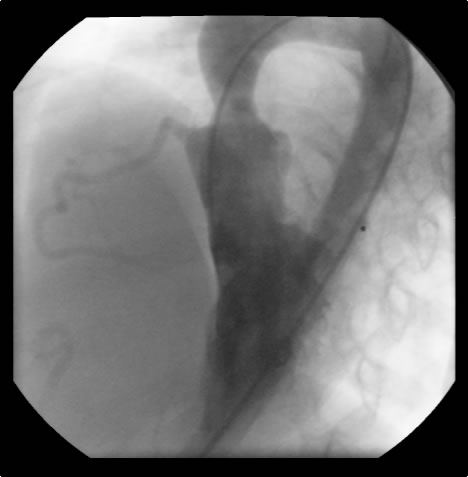

Figure 2: Preoperative cardiac catheterization. Figure 3:The "waist" in the ascending aorta is readily apparent. The "waist" is above coronary orifices. Figure 4: AP/Lateral ventriculogram. The patien has no subaortic obstruction. Figure 5: Main pulmonary artery injection. There is no peripheral pulmonary artery stenosis.